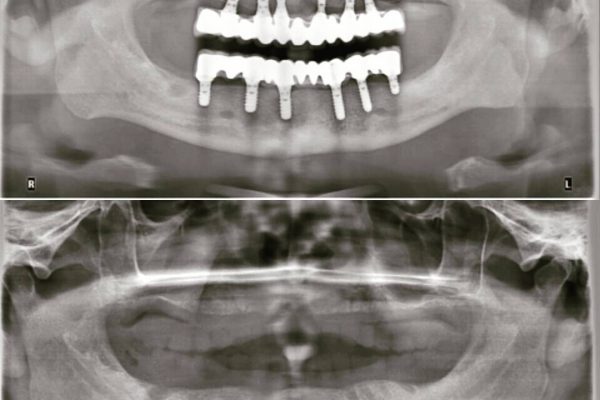

Zahnimplantate

In unserer Partner Klinik werden

bereits

über 10.000

Implantate

eingesetzt.